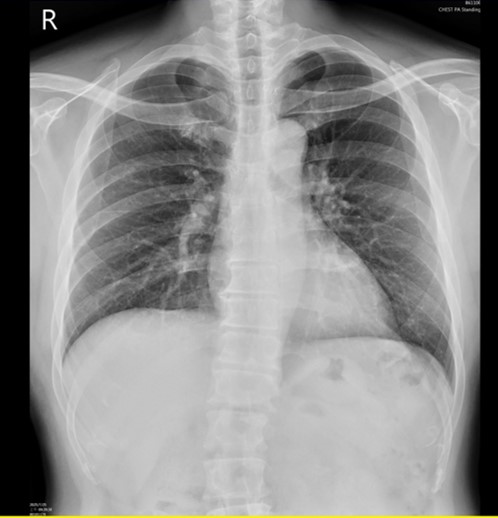

The third CCTA of the patient was performed on July 1, 2025 and showed calcium scores was 213 points (Fig 1) and coronary artery ectasia (CAE) of RCA and a 90% stenosis with high risk plaque with low-attenuation density and positive remodeling and spotty calcification at middle RCA (Fig 2 and 3) and a 80% stenosis with focal calcification and stable plaque at distal RCA. So regarding his RCA lesions of CCTA finding, the patient received coronary artery angiogram and coronary intervention.